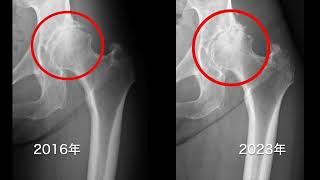

今日は骨切り手術の成績についてご紹介します。

最近になって骨切り手術をし、30年~40年と比較的経過の長い方からご相談をいただくことが多くなりました。人工関節も同様ですが、手術をしても不安や悩みは尽きません。学術的には良好(レントゲン画像や痛みなど)との判断であっても、皆さん個々に問題を抱えていらっしゃいます。